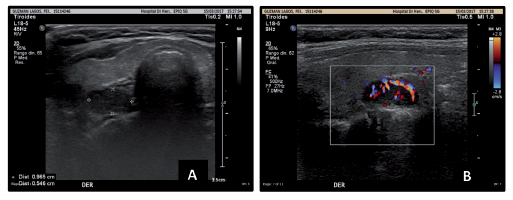

Adolescente masculino de 11 años, previamente sano. Presenta historia de tres meses de constipación y anorexia. A los dos meses, se agregan náuseas, vómitos y pérdida de peso de 10 kg. Acude a Servicio de Urgencia, se solicitan exámenes, destacando: calcemia 16,67 mg/dl (VN 8,8-10,8 mg/dl) y fosfemia 2,21 mg/dl (VN 4,5-5,5 mg/dl). Ingresa a Servicio de Pediatría de Hospital Hernán Henríquez Aravena, para manejo y estudio. Se inicia hiperhidratación, fostato monopotásico, hidrocortisona y furosemida intravenosos (iv). En exámenes (Tabla 1), destaca: PTH 308,7 pg/ml (VN 15-68,3 pg/ml), calcemia de 13,2 mg/dl (VN 8,8-10,8 mg/dl) y fosfemia de 2,7 mg/dl (VN 4,5-5,5 mg/dl), índice calciuria/creatininuria 0,56 (VN < 0,2). Se realiza ecografía cervical que muestra PT derecha con nódulo sólido, hipoecogénico, de contornos delimitados, vascularizado al Doppler de 9,6 por 5,4 por 12 mm (Figura 1), por hallazgo se solicita cintigrama paratiroideo con Tecnecio 99 metaestable (Tc99m)-Sestamibi, destaca foco de acumulación de Sestamibi en polo superior del lóbulo tiroideo derecho, probable adenoma paratiroideo (Figura 2).

Figura 1. Ecografía cervical. A. Glándula paratiroides derecha con nódulo de aspecto sólido, hipoecogénico, de contornos bien delimitados de 9,6 por 5,4 por 12 mm de diámetro. B. Nódulo antes descrito se observa vascularizado al Doppler.

Para evidenciar glándulas aumentadas de volumen y si la alteración es única o múltiple, se realiza estudio imagenológico que comprende ecografía cervical y cintigrafía con Tecnecio 99 metoxi-isobutilnitrilo-Sestamibi (Tc99m-Sestamibi). En la primera, los adenomas se observan como nódulos ecoicos homogéneos, altamente vascularizados al Doppler. Tiene una sensibilidad de 86%, especificidad de 67% y un valor predictivo positivo de 95% en identificación de glándulas adenomatosas e hiperplásicas8,9.